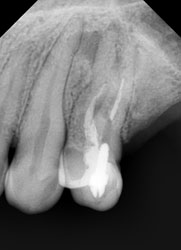

На этом рентгеновском снимке видны, в первую очередь, «пустые» корневые каналы и довольно больших размеров очаг воспаления (то, что часто называют гранулемой, кистой) на верхушке одного из корней. В общем итоге в одном зубе был сконцентрирован целый букет ошибок и недоделок, одним словом, это образец недобросовестной работы стоматолога. Я стараюсь о коллегах всегда говорить или хорошо или молчать, но в данном случае надо смотреть правде в глаза – зуб загублен именно стоматологом. Никаких объективных сложностей для качественной работы изначально здесь не было. Зато появились теперь. Прогноз на будущее для таких зубов всегда строится, исходя из 2 основных проблем – насколько приведет к успеху повторное лечение каналов и насколько будет успешной попытка адекватного восстановления зуба после этого. Оценив вероятность долговременного успеха этих двух составляющих, можно решать, стоит ли «спасать» зуб от щипцов хирурга. Ведь, в любом случае, лечение стоит денег, а гарантировать результат здесь невозможно. Можно только предполагать вероятность успеха. В данном случае каналы не выглядели непроходимыми. Да и восстановить зуб коронкой, даже несмотря на большую степень разрушения, все еще представлялось возможным. А потому было принято решение о начале лечения.